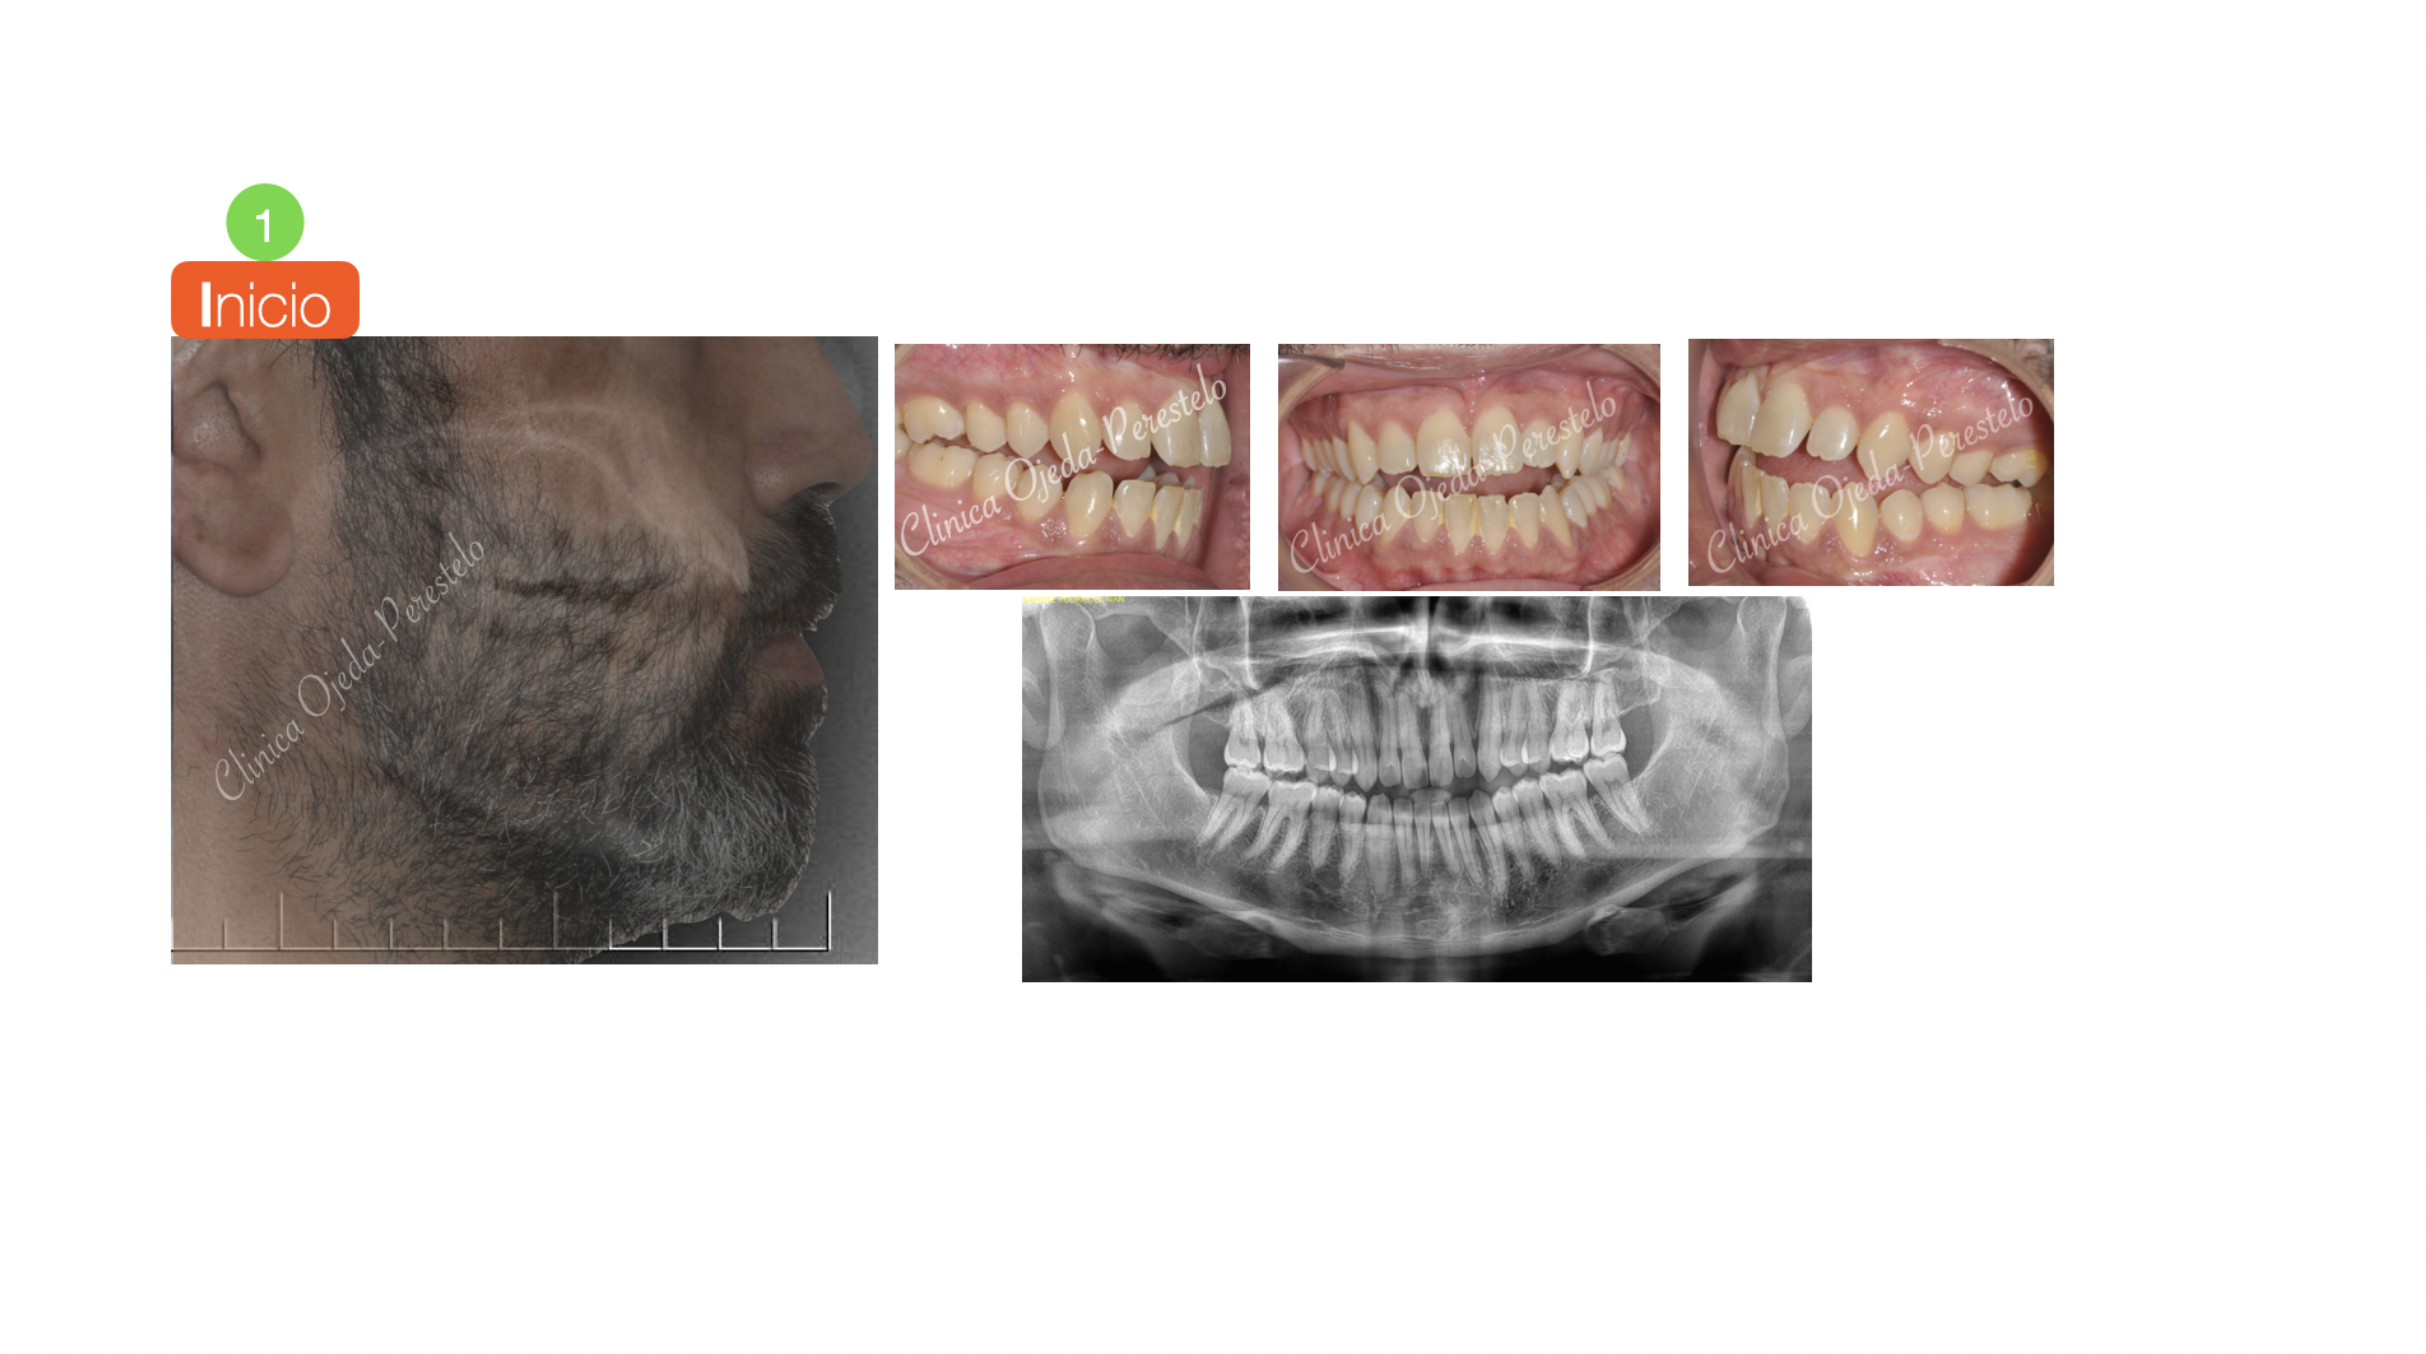

Mordida Abierta de molar a molar

Los alineadores son una excelente opción terapéutica en aquellos pacientes con mordida abierta. Presentamos un caso severo donde se realizó el cierre de la mordida con alineadores transparentes y Microtornillos combinado intrusión posterior con extrusión anterior. También realizamos el desarrollo transversal (expansión) de las arcadas.

En nuestra experiencia la mordida  abierta se cierra más eficientemente con alineadores transparentes que con Ortodoncia fija (brackets).

Se ha alcanzado el objetivo con 34 alineadores Maxilares y 33 Mandibulares con cambio semanal en un tiempo de 8 meses y medio.